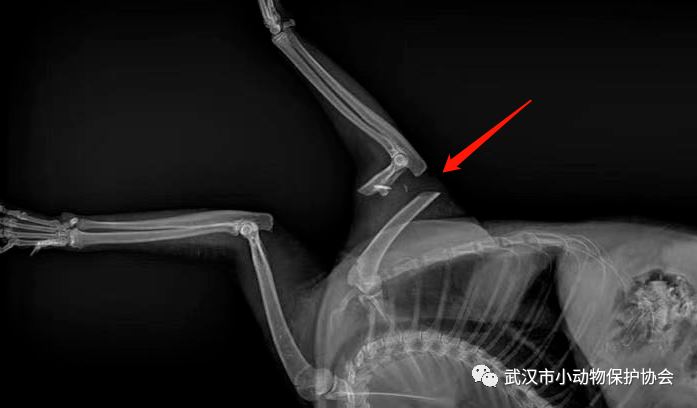

发现人联系我们说,她在高架桥上救下了一只猫咪,带回家后发现小家伙的腿断了,送去宠物医院做了检查,拍片子一看,猫咪的腿严重断裂。